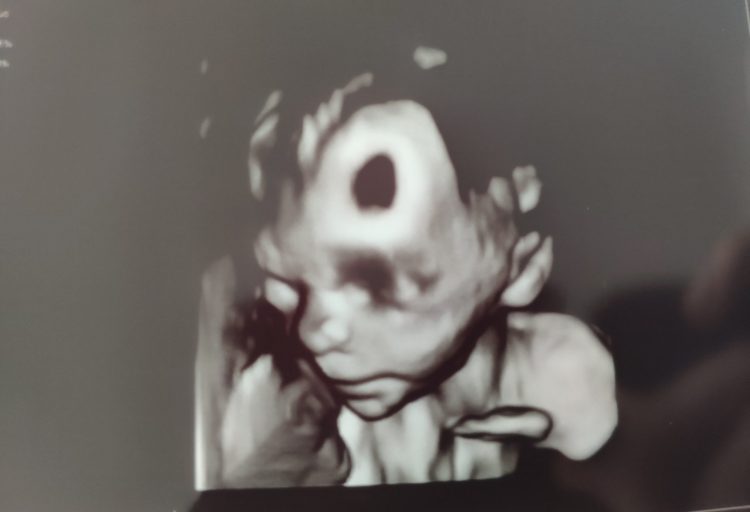

Genau deshalb liege ich seit Sonntag im Krankenhaus und heile. Bewegung war zuerst verboten, heute aber gibt’s immerhin schon grünes Licht für Treppensteigen und Spaziergänge. Beobachtung unter Belastung nennt man sowas, worunter ich mir eigentlich eher sowas wie Tauziehen mit der Ärzteschaft vorgestellt hatte – oder ein Wettrennen mit dem Chefarzt.

Naja, man kann nicht alles haben. Viel wichtiger ist ja ohnehin: Wenn morgen alles ok aussieht im Ultraschall, dann darf ich heim. Drückt mir die Däumchen. ☺️